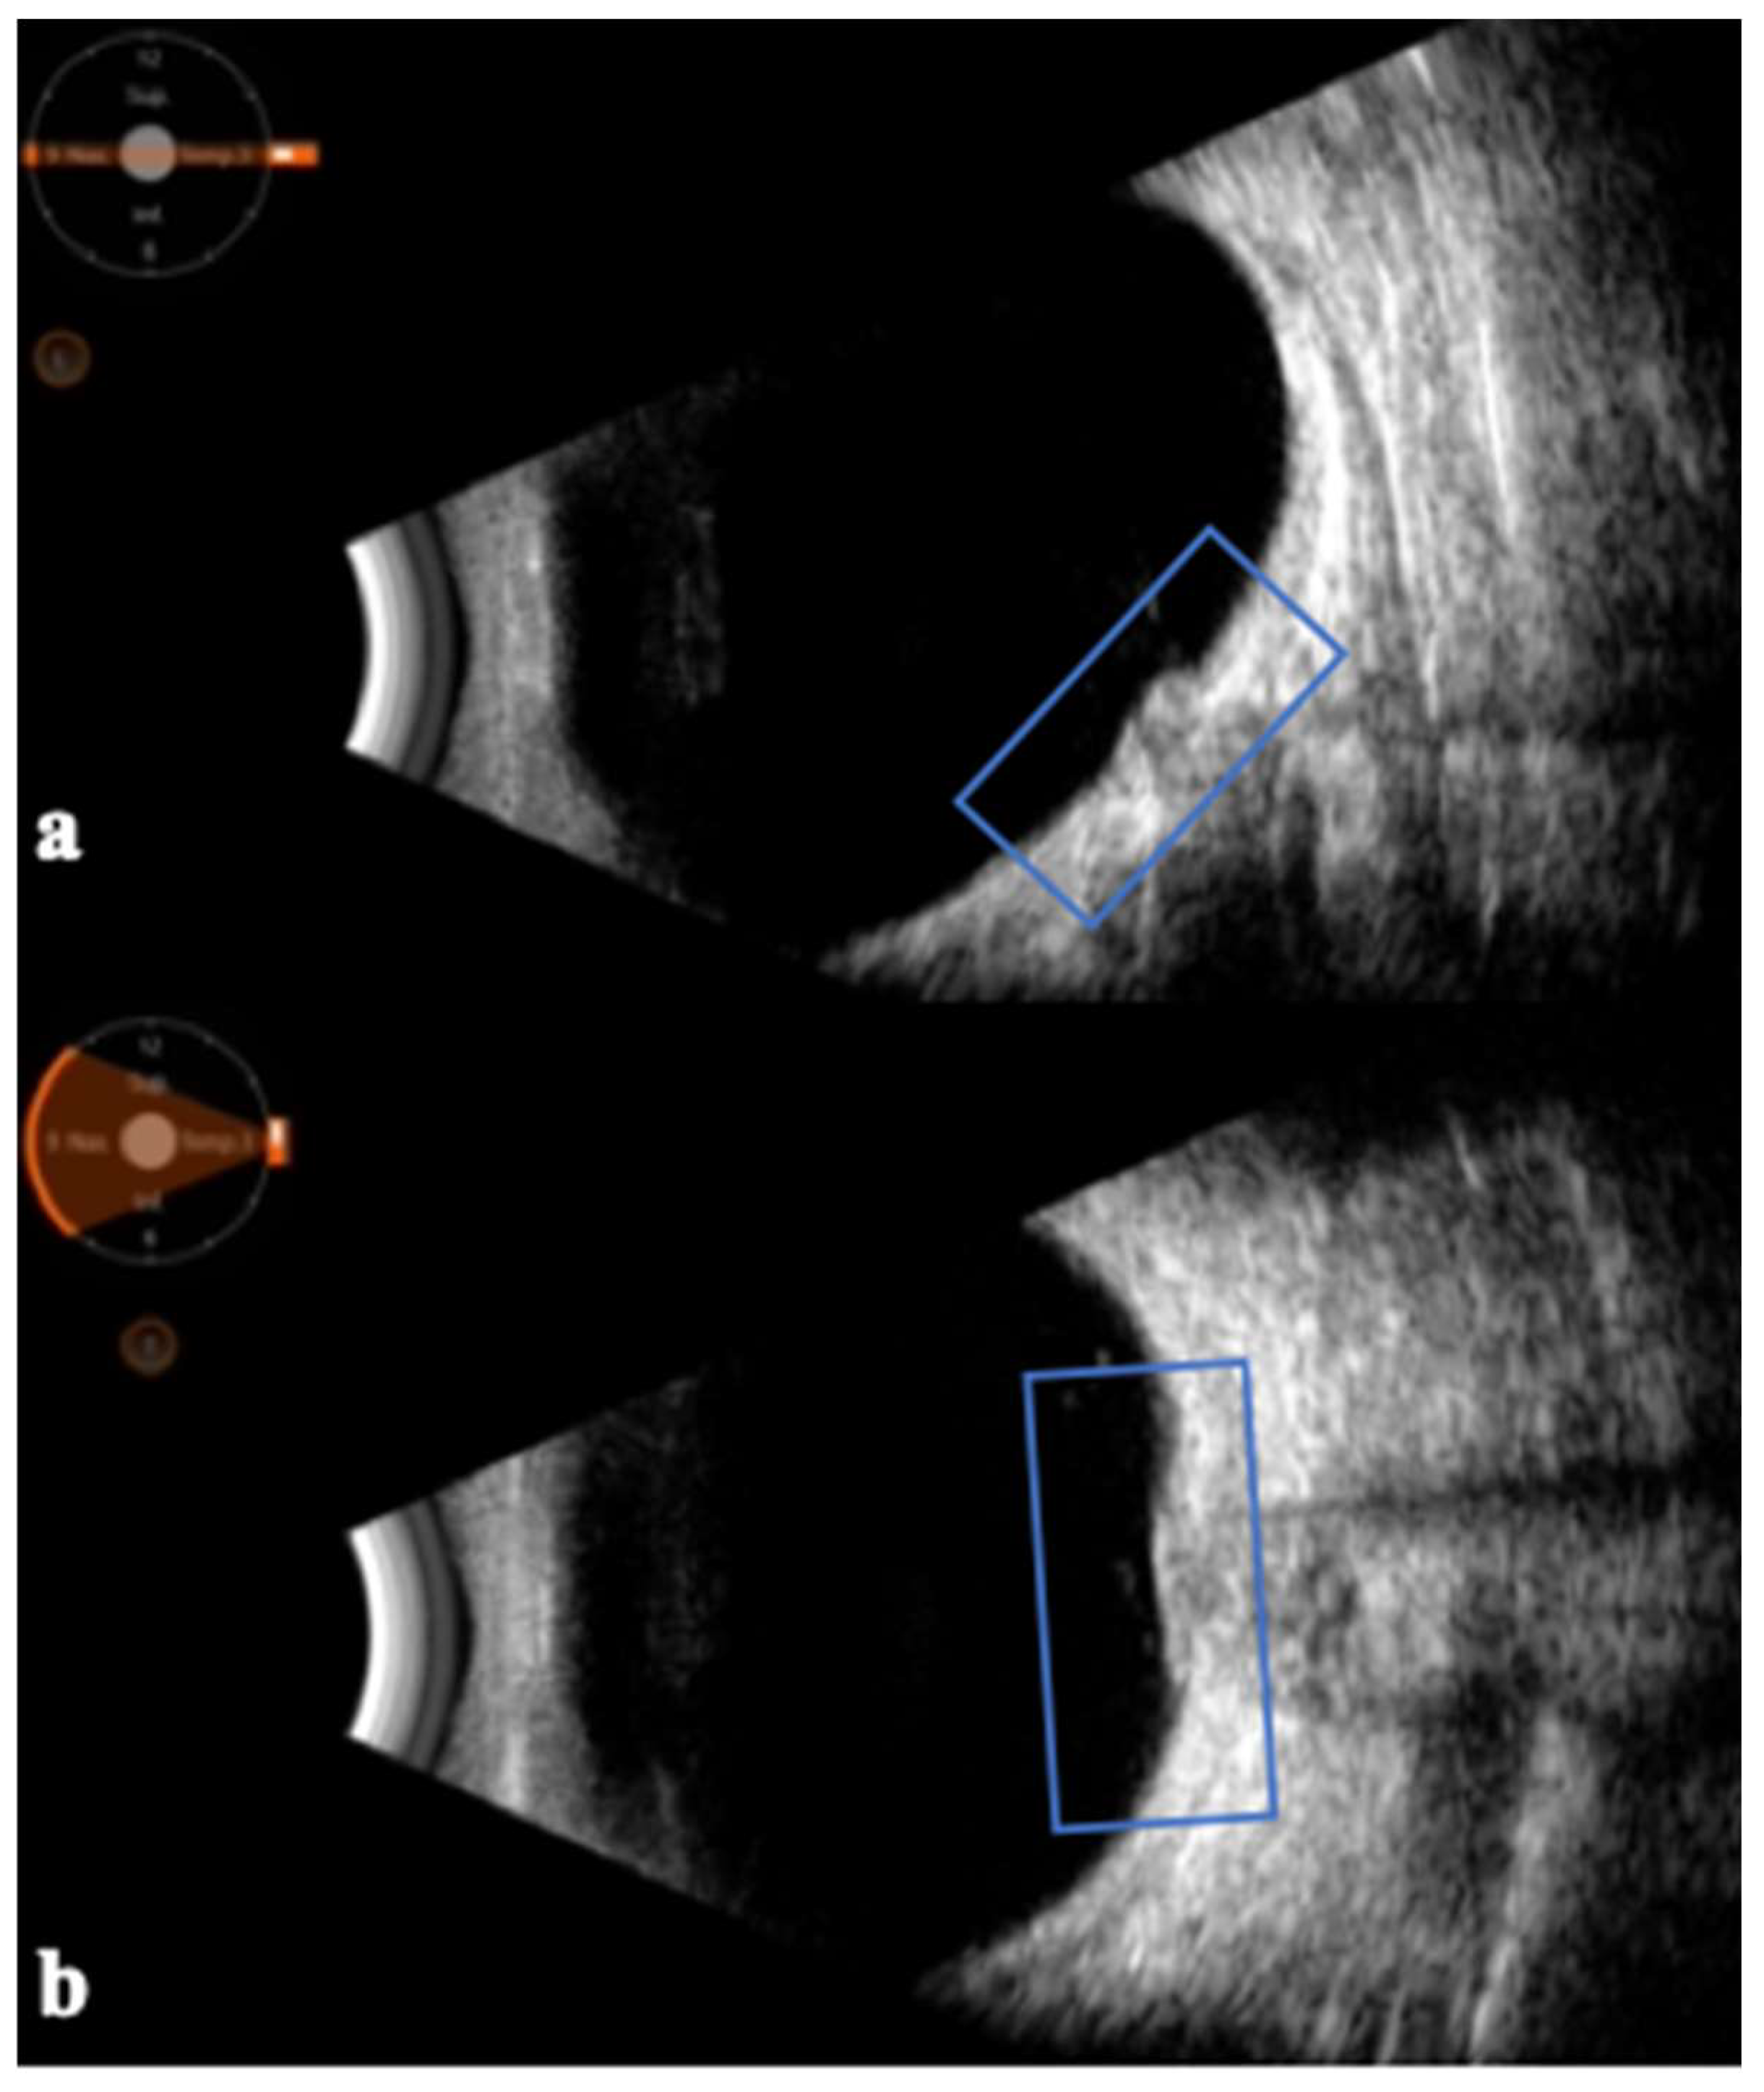

- Lochner, P.; Cantello, R.; Brigo, F.; Coppo, L.; Nardone, R.; Tezzon, F.; Raymkulova, O.; Strigaro, G.; Comi, C.; Leone, M.A. Transorbital sonography in acute optic neuritis: A case-control study. AJNR Am. J. Neuroradiol. 2014, 35, 2371–2375. [Google Scholar] [CrossRef] [PubMed]

- Lochner, P.; Leone, M.A.; Fassbender, K.; Cantello, R.; Coppo, L.; Nardone, R.; Zorzi, G.; Lesmeister, M.; Comi, C.; Brigo, F. Transorbital Sonography and Visual Outcome for the Diagnosis and Monitoring of Optic Neuritis. J. Neuroimaging 2017, 27, 92–96. [Google Scholar] [CrossRef]